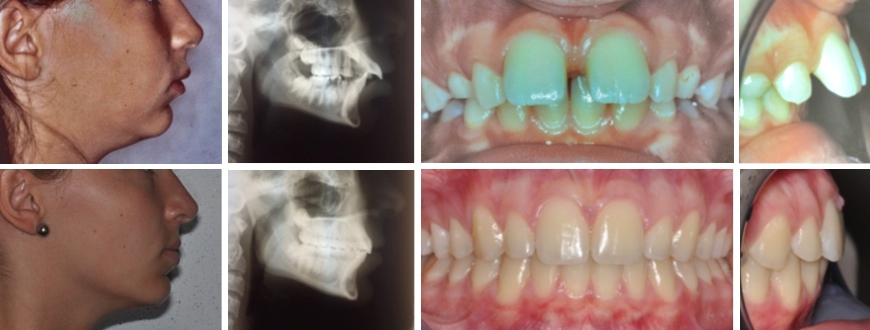

Fall 1: Vergrösserter Überbiss durch Unterkieferrücklage

Therapie: Nachtspange und festsitzende Spange